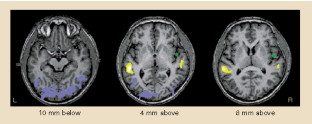

The upper regions of the brain's temporal lobe are important both for hearing and for comprehending spoken language. We have discovered that these regions can be activated by sign language in congenitally deaf subjects, even though the temporal lobe normally functions as an auditory area. This finding indicates that, in deaf people, the brain region usually reserved for hearing may be activated by other sensory modalities, providing striking evidence of neural plasticity.